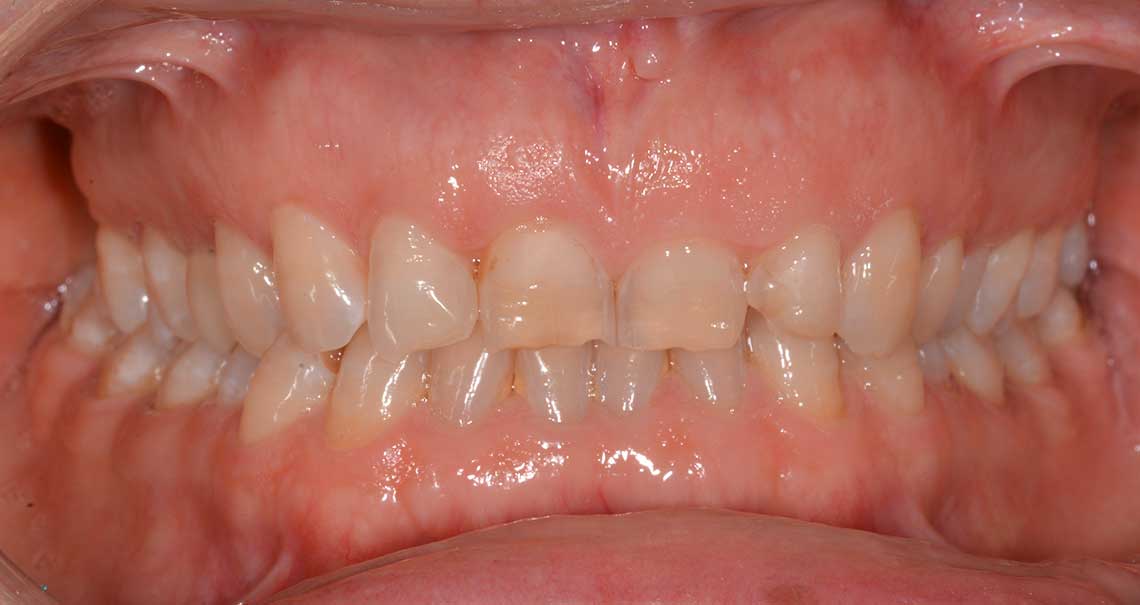

Ortodonzia allineatori – caso clinico 2